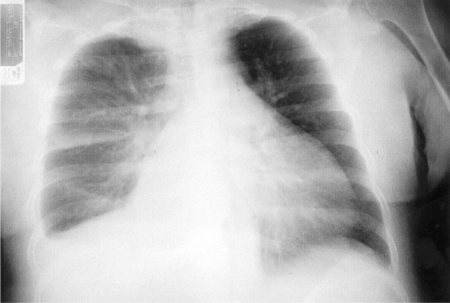

Acute exacerbation of congestive heart failure

Acute cardiogenic pulmonary oedema results from increased end-diastolic left ventricular pressure and presents with dyspnoea worsened by exertion, orthopnoea and paroxysmal nocturnal dyspnoea, elevated neck veins, peripheral fluid retention, an S3 gallop rhythm on cardiac auscultation, and pulmonary congestion (fine bibasal rales) on chest auscultation. The patient may have a history of heart failure.

Typical chest x-ray features include characteristic signs of pulmonary venous congestion, and there may be cardiomegaly.[Figure caption and citation for the preceding image starts]: Chest x-ray of acute pulmonary oedema showing increased alveolar markings, fluid in the horizontal fissure, and blunting of the costophrenic anglesFrom the private collections of Syed W. Yusuf, MBBS, MRCPI, and Daniel Lenihan, MD [Citation ends].